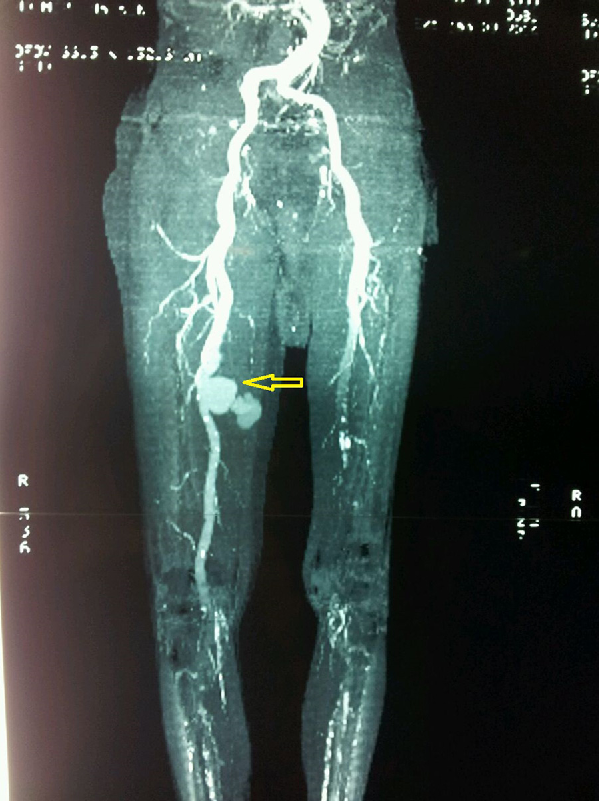

Femoropopliteal (fem-pop) bypass surgery is used to bypass diseased blood vessels above or below the knee.

To bypass the narrowed or blocked blood vessel, blood is redirected through either a healthy blood vessel that has been transplanted or a man-made graft material. This vessel or graft is sewn above and below the diseased artery so that blood flows through the new vessel or graft.

The section of vein or man-made blood vessel graft is sewn onto both the femoral and popliteal arteries so that blood can travel through the new graft vessel and around the narrowed or blocked area.